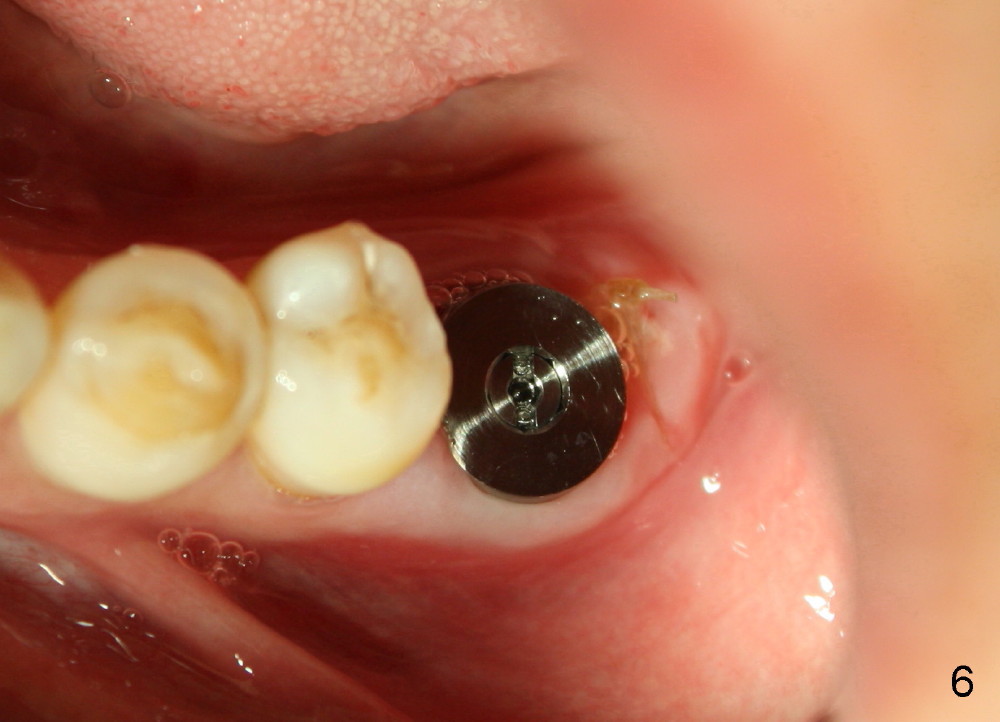

Seven days later, there is no sign of infection around the implant (Fig.6). Chronic infection prior to extraction may recruit our defense mechanism (such as white blood cells), which help prevent posteop infection. Two months postop, the gingiva is healthy around the implant (Fig.7,8).